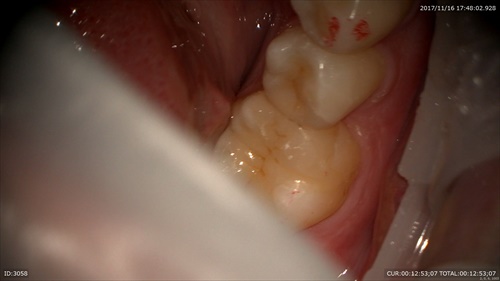

セラミックの詰め物ケース

前回神経を保護する治療を行い。

「最初はしみていたけど、今は良くなった」と喜んでいました。

研磨

セット。おいしい物沢山食べてください!!